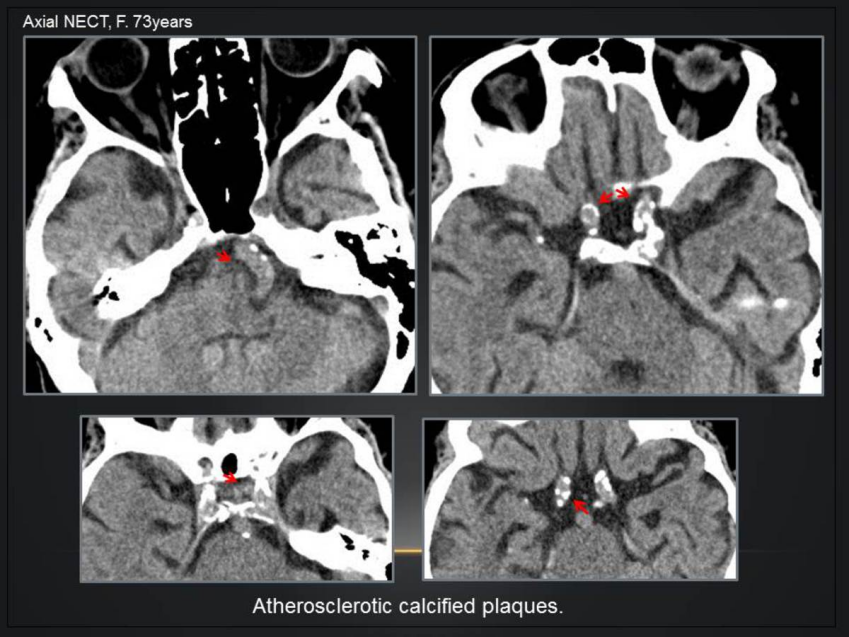

3.血管相关:动脉粥样硬化、动脉瘤、动静脉畸形、静脉发育不良、海绵状血管瘤、动静脉瘘

98d5526d99a8a6d113ec435f336e8add.png

动脉粥样硬化,颅内大动脉壁结节状或线样钙化